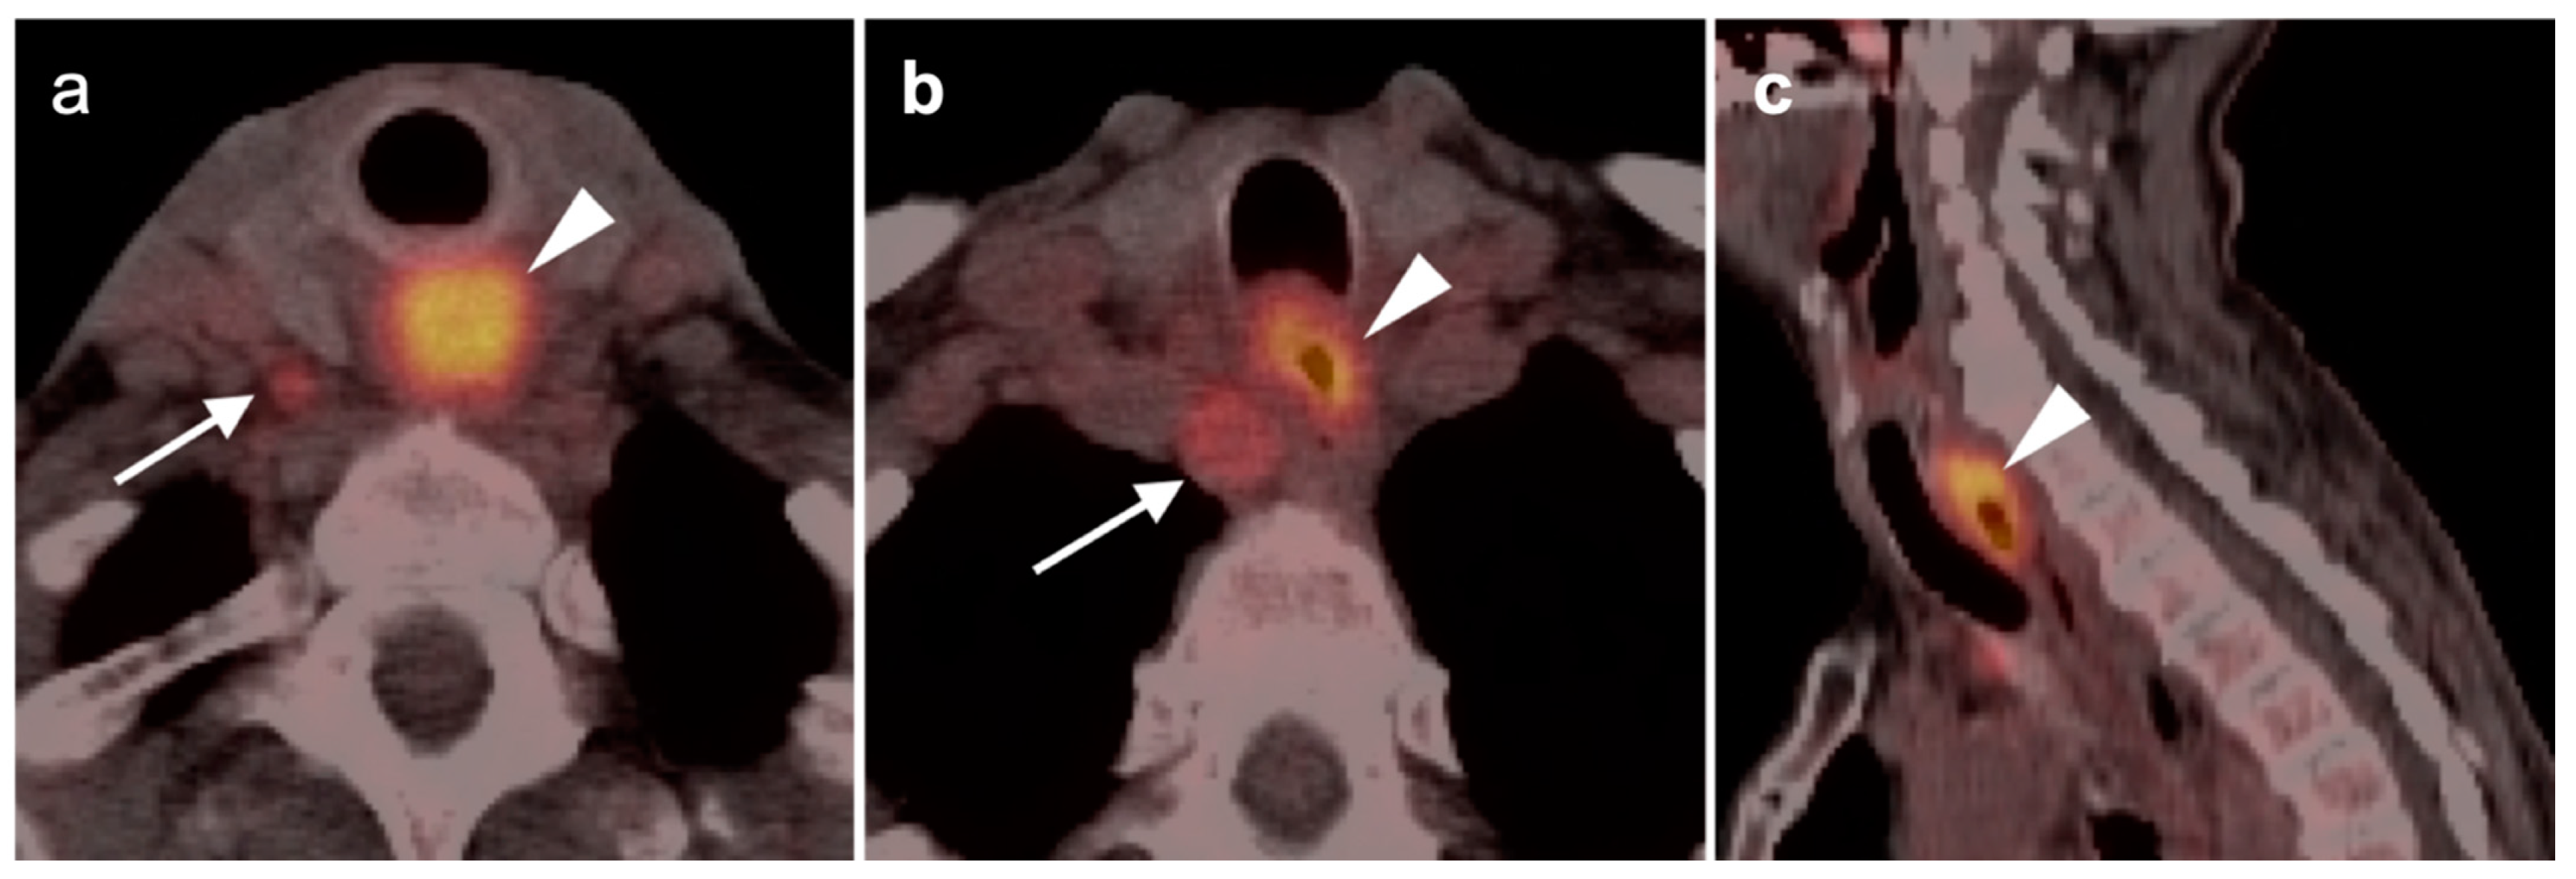

2.6. Thyroid Cancer

- Differentiated thyroid cancer

- Anaplastic thyroid cancer

- Medullary thyroid cancer